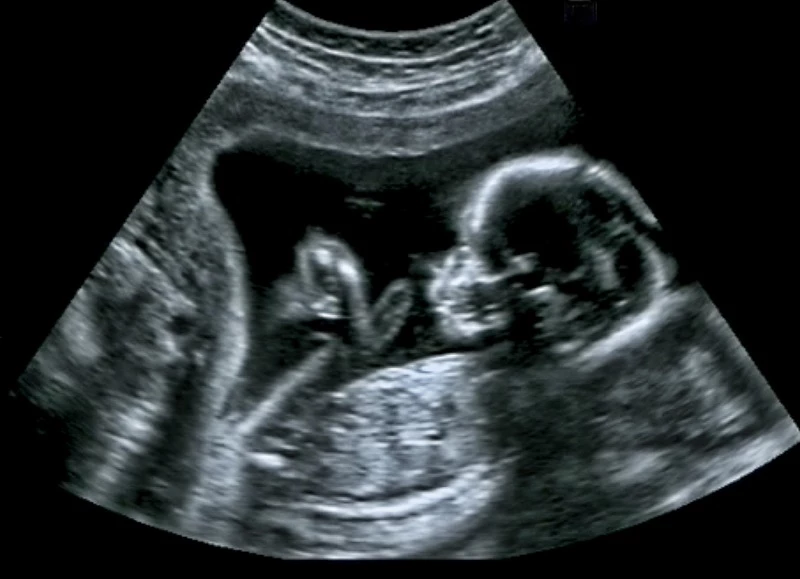

사건은 7년 전으로 거슬러 올라가는데, 임신 18주 차를 맞은 베키 터너는 다리에 알 수 없는 고통을 느껴 병원에서 검사를 받았으나 결과는 심각했다.

몇 달 뒤 베키는 사랑스러운 딸을 출산했고, 감염 부위가 확산되는 것을 막기 위해 출산 이후 다리를 절단해야 했다.

베키의 딸은 건강하게 자라 이제 7살이 됐다.